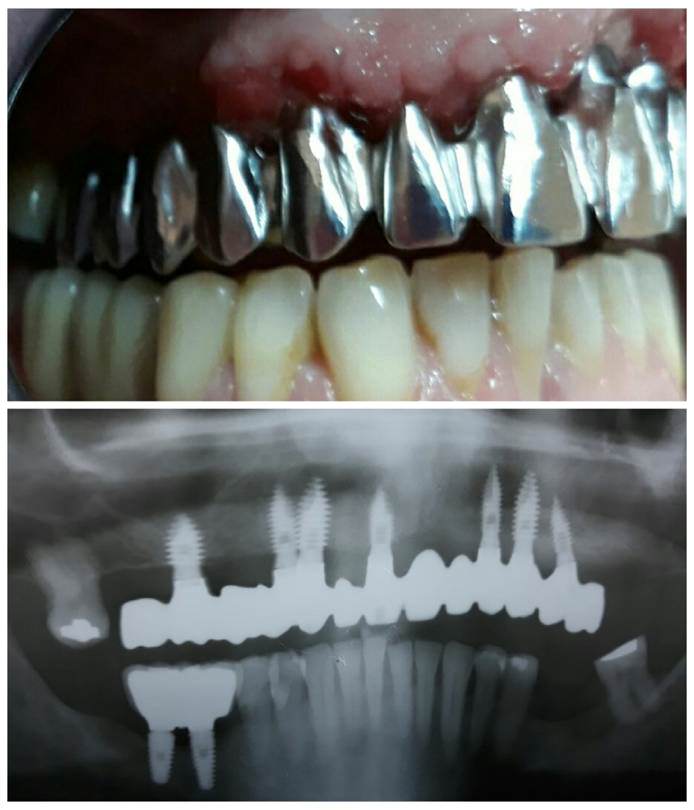

Se programa cirugía para la inserción de 7 implantes superiores para carga inmediata . El mismo día de la de la cirugía se toman las impresiones, que son enviadas a laboratorio. Procedemos a la fabricación de una prótesis híbrida provisional. 24 horas después de la cirugía, el paciente sale de la clínica con su prótesis superior atornillada . Esta prótesis será funcional durante todo el proceso de fabricación de la rehabilitación definitiva . En la fabricación vemos que la emergencia de 2 de los implantes anteriores es vestibular, lo cual nos exige angular al menos esos 2 pilares (11 y 13).. También nos alerta a nivel de estética ya que los dientes superiores apenas son visibles.

Se añaden canales de angulación a las piezas 11 Y 13 para que la emergencia sea palatina y también se angula la pieza 26 para mejorar la vía de inserción. Una vez registrados todos los parámetros y hecha la reducción del encerado diagnóstico procedemos a fresar la estructura en Cr-Co.

AJUSTES DE ESTRUCTURA

Con la estructura ya fresada comprobamos que los ajustes a los análogos son correctos y que la estructura atornillada está libre de tensiones. Mandamos la estructura a clínica para prueba radiológica y gingival realizada por la Dra. Mónica Paupie, la cual nos confirma que los ajustes son correctos.